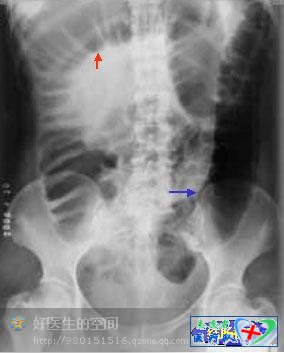

梗阻发生3-6小时后,出现梗阻近端肠曲扩张、积气(红箭头)、肠内有高低不等的阶梯状气液平面(蓝箭头)。

梗阻发生3-6小时后,出现梗阻近端肠曲扩张、积气(红箭头)、肠内有高低不等的阶梯状气液平面(蓝箭头)。根据积气扩张的肠管形态可判断梗阻的大体部位,空肠呈鱼肋状,回肠呈光滑管状,结肠可见结肠袋。空肠段以上梗阻为高位肠梗阻,回肠段以下梗阻为低位肠梗阻。